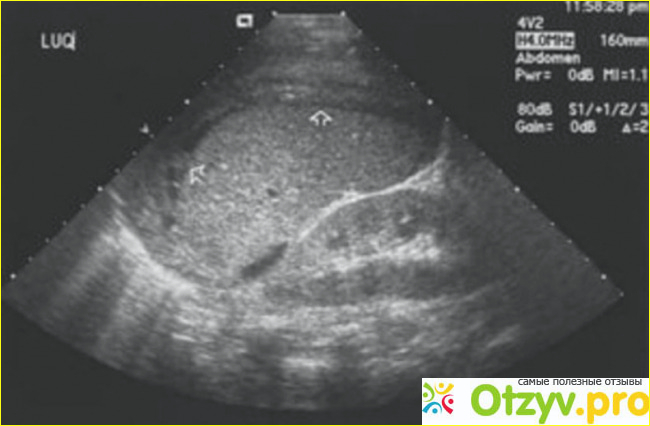

Процедура УЗИ желудка безболезненная и не вызывает никакого дискомфорта. Пациент просто ложится на кушетку или в полусидячем положении, оголяет область живота. Врач-диагност наносит на исследовавшую область желудка специальным гелем, который поможет быстро скользит датчику. После этого врач водит по области желудка валикообразным аппаратом, а то, что исследуется показывается картинкой на компьютере. Более того, современная техника дает возможность не только увидеть картинку, но и услышать, что там происходит. А видно все очень хорошо, но вот только расшифровать может только человек, у которого есть специальное образование. Во время процедуры пациент не чувствует никаких болевых ощущений, никакого ощущения дискомфорта. В общем, все это проходит нормально, без каких-то либо проблем!

Процедура длитс 10 - 20 минут. В частных клиниках это делается намного быстрее. По окончанию процедуры врач дает заключение и ставит диагноз, поскольку он записал все параметры и показания обследования желудка. Самостоятельно расшифровать все данные исследовании невозможно и не рекомендуется, ведь можно поставить себе как минимум неправильный диагноз, обязательно надо обратится за заключением к врачу.